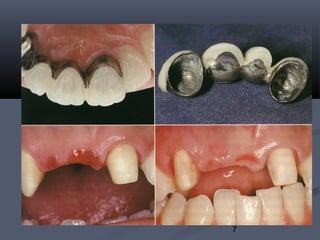

Loose ¾ retainer on canine

Carious canine in need of

root canal treatment

¾ retainer was cut and the

remaining bridge cemented